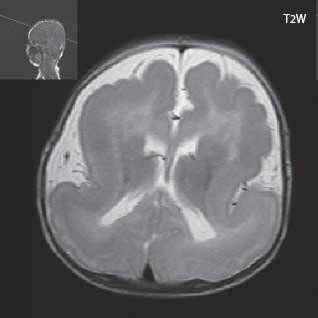

Rozšíření subarachnoidálních prostorů na konvexitě v prvním roce života. V 1. roce života můžeme u dětí pozorovat nález, který lze považovat za ještě fyziologický rozšíření subarachnoidálních prostorů na konvexitě, někdy i diskrétní rozšíření mozkových komor. Příčinou je nejspíše diskrepance mezi růstem lebky a mozku, svoji roli může také hrát nevyzrálost Pacchionských granulací (vstřebávají likvor do žilního oběhu), které jsou plně funkční ke konci 2. roku života.

Obr. I.1.1f Rozšířené subarachnoidální prostory (věk 6 měsíců – v tomto období se nejedná o patologický stav, ale jsou fyziologicky prostornější)

Obr. I.1.1g Rozšířené subarachnoidální prostory (věk 6 měsíců – v tomto období se nejedná o patologický stav, ale jsou fyziologicky prostornější); stejný pacient jako na obr I 1 1f

f g h ch

Obr. I.1.1h Fyziologický nález, již normální šíře subarachnoidálních prostor (věk 1,5 roku); stejný pacient jako na obr I 1 1f, g

Obr. I.1.1ch Fyziologický nález, již normální šíře subarachnoidálních prostor (věk 1,5 roku); stejný pacient jako na obr I 1 1f, g, h